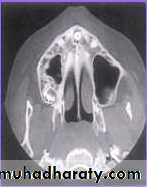

CBCT

Cone beam

computedtomography

(or CBCT, also

referred to as C-arm

CT, cone beam

volume CT, or flat

panel CT) is a

medical imaging

technique consisting

of X-ray computed

tomography where

the X-rays are

conventional radiography does

information.76

not provide sufficient

CBCT is more accurate than

conventional techniques inlocalising impacted maxillary

canines.

CBCT is more reliable than

conventional techniques There is no robust evidence

that supports using CBCT as

the first line imaging technique.

We should only use it when

Cone-beam computed tomography vs conventional radiography in visualization

of maxillary impacted-canine localization: A systematic review of comparativestudies. Ehsan Eslami et al. Am J Orthod Dentofacial Orthop 2017;151:248-58

A study was done by Ali Alqerban et al AJODO March

2015, to compare 3D CBCT images of unilaterally

impacted canines with the normal contralateral sides,

and to detect possible radiographic factors involved in

maxillary canine impaction.

Prediction of the probability of canine impaction based

on CBCT was excellent. The canine angulation to the

lateral incisor on the coronal view, the canine cusp tip to

the occlusal plane on the sagittal view, and the canine

crown position were the strongest predictors based on

the CBCT radiographs and may help orthodontists to

identify the probability of impaction for optimally timing

the intervention.

Cone-beam computed tomographyand the orthosurgical management of impacted

teethCBCT imaging can be used to interpret buccolingual

information in detail, to distinguish and define the extent and

depth of root resorption, and to delineate long-axis orientation

of unerupted teeth, including root apex location. It is able to

synthesize traditional panoramic and cephalometric

radiographs. permits oral surgeons to visualize the position

and surgical anatomy of the tooth as it will be seen in the

operating theater and allows orthodontists to plan directional

traction.